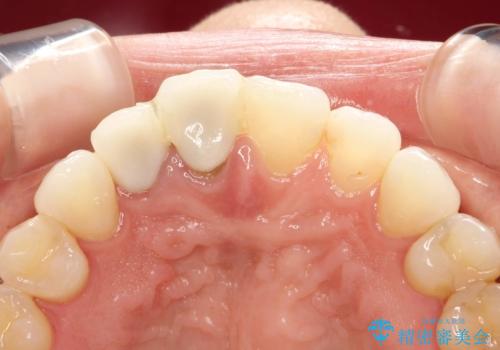

前歯がぐらぐらする 抜歯→ブリッジへ

古いかぶせ物は土台ごと歯から脱落してしまっており、歯の内面には複数の亀裂が入っている状態でした。残存歯質が非箔であることと、動揺の程度から、やむを得ず抜歯→ブリッジという方法を選択していただき、歯根挺出を用いることでなるべく前歯の骨の陥没を防ぎ、ブリッジを製作しました。

かぶせ物の種類:PFZ standard